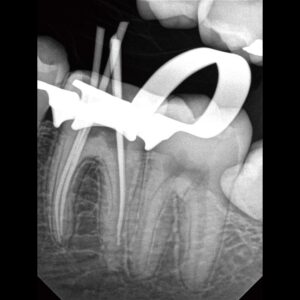

Exceptional image quality and robust durability intraoral–imaging device

Designed for precision and consistent performance, our intraoral sensor offers unparalleled comfort and quality. This long-lasting, reliable sensor is designed to withstand the daily stresses of dental practice.

The intraoral sensor that does it all

Our sensors are tailored to fit perfectly, further enhancing the patient’s comfort during the imaging process. Whether it’s a child or an adult, our sensors are designed to fit perfectly.